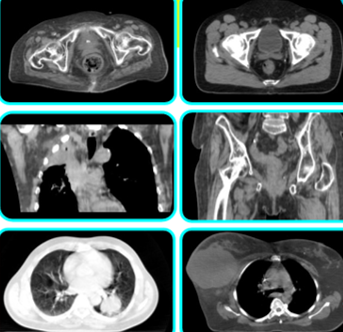

内蔵CTで照射前に画像確認

高精度な画像誘導放射線治療(IGRT)機能を備えており、毎回の治療前に内蔵CTで体内の画像を取得し、腫瘍の位置を正確に確認し、補正してから照射を実施します。これにより、体のわずかな動きや日々の変化にも対応ができ、常に狙った場所に正確な位置への照射が可能となります。従来よりも位置ずれのリスクが低減されるため、不要なマージンを減らして正常組織への影響を最小限に抑えながら、安全で効果的な治療を実現します。